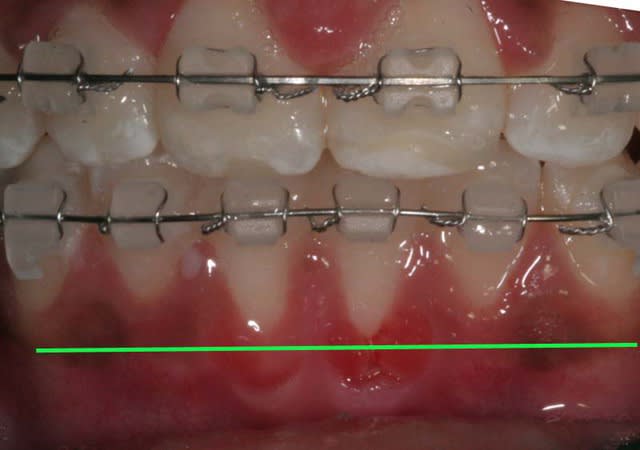

Voici un cas de béance associé à un Pb. paro sur 31/41

Est-ce qu’un traitement ODF. ne vas pas aggraver cette perte de gencive attaché (et osseuse),

et faut-il faire des extractions pour replacer 31/41 dans le massif osseux et arrêter cette récession ?

Fermeture de la béance par reformage des arcades tout en surveillant 31/41 que je traite par surfaçages et Kayes tous les mois

je prescris une brosse chirurgicale pour 31/41, la motivation de l’enfant et des parents est excellente

A suivre